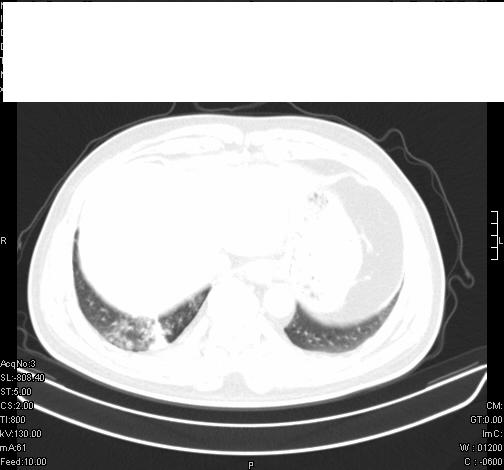

标题: CT6685:右肺阻塞性炎症,增强CT。

前几天,发了患者的平扫片,患者抗炎一周后增强扫描。右中叶病灶吸收明显,但下叶病灶未见明显吸收。右肺门可见结节影,看来凶多吉少

右肺下叶支气管管腔狭窄,管壁增厚,右下肺见斑片状高密度影,考虑右侧肺门中心肺癌伴阻塞性肺炎

右肺下叶散在的斑片状致密影,下叶支气管变窄。考虑:右肺慢性炎症。

右肺下叶支气管壁不规则增厚,右肺下叶有斑片状影分布。考虑右肺中央型肺癌伴右肺下叶阻塞性改变。建议支纤镜检查。平扫比增强较好显示了病变情况。

既然抗炎治疗有效,可继续治疗;右肺下叶支气管管腔狭窄,管壁增厚,右下肺见斑片状高密度影,右侧主支气管后见结节影(淋巴结?),肺癌不能排出。